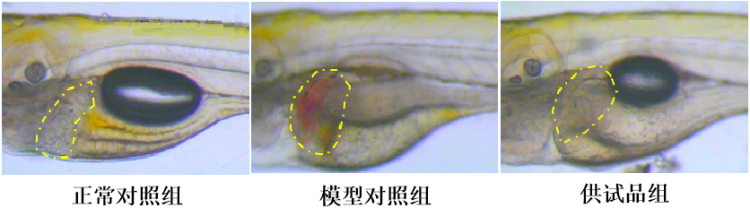

图1. 斑马鱼肝脏出血表型图

(绿色虚线区域为斑马鱼肝脏,绿色箭头指向肝脏出血部位)

从实验结果可以看到,服用供试品组斑马鱼与模型对照组比较,肝脏出血现象减少。